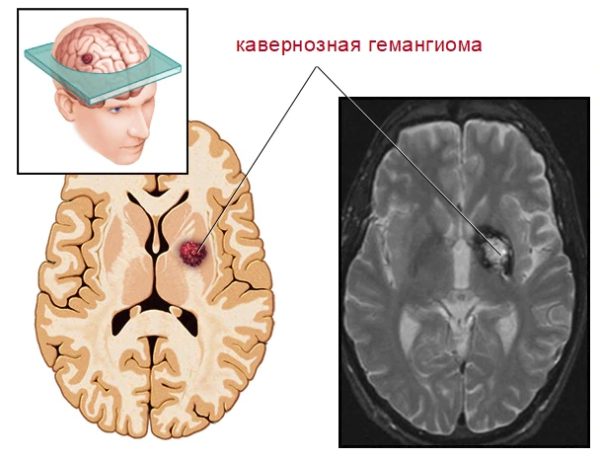

Мр картина венозной ангиомы левой гемисферы мозжечка - 96 фото